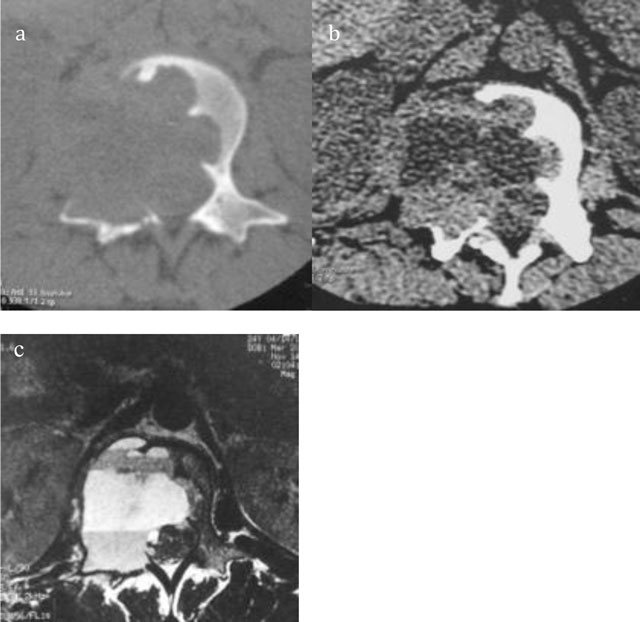

Figure 6

Giant Cell Tumor of L2. Axial CT scan of L2 shows a multiloculated lytic lesion (a) with intralesional fluid–fluid levels (b). Axial T2-WI MRI confirms an expansile multiloculated lesion of the body and neural arch containing fluid-fluid levels (c).